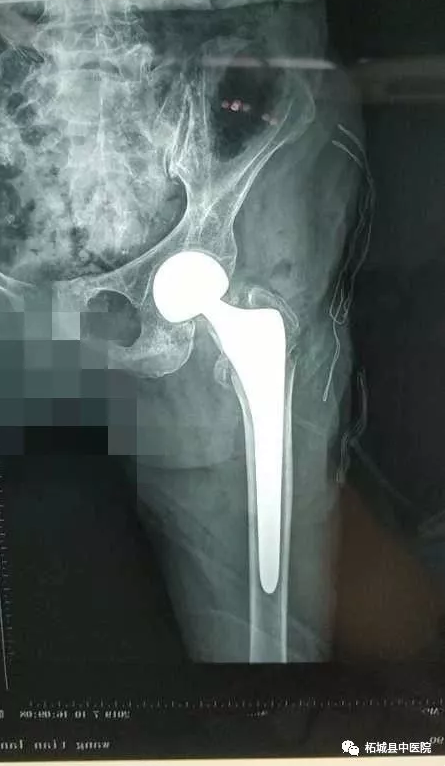

7月10日下午,在中医院北关院区百级层流净化手术室,殷晓东院长带领骨二科医师团队亲自手术,麻醉师张文选全程监控,内科专家王因仲、孙全立随时待命。仅耗时20分钟就顺利地完成了主操作。当老人被平安送出手术室的一刻,柘城中医院乃至柘城县 高龄髋关节置换手术患者的纪录也再次被刷新。